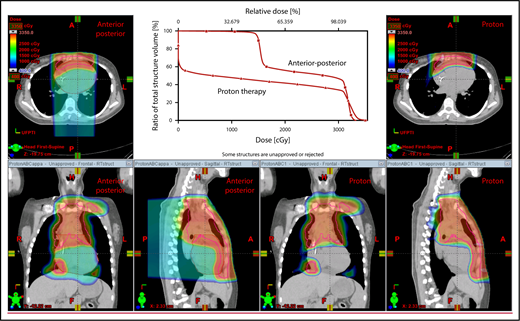

With regard to field arrangements, the PBSPT technique for an anterior upper mediastinal and lower neck target usually requires 1 (repainted) or 2 anterior fields. For more complex target volumes, targets can be divided into 2 or more parts (eg, neck CTV, mediastinal CTV, and axillary CTV), and a multifield plan can be used (Figure 5). For cases that involve lower (posterior) and upper (anterior) mediastinal targets, a combination of posterior and anterior fields can maximally spare the heart and lungs (Figure 6). For upper neck targets, lateral or posterior fields can avoid the oral cavity/salivary structures. For axillary targets, a posterior field can help to spare breast tissue. Although these various field arrangements can be used in PSPT, gradient matching is simpler in PBSPT when the fields overlap or oppose, obviating the need for feathering.

Scans for a young woman in whom the target included mediastinal, left parasternal, and left axillary regions. One anterior field was used for the mediastinum, and a separate posterior field was used for the axillary region.